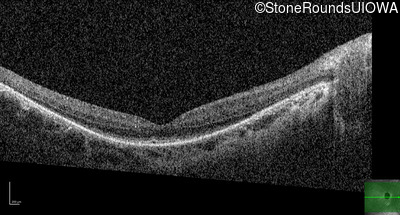

OS

20/70 -2

20/80 -1

OCT Stack